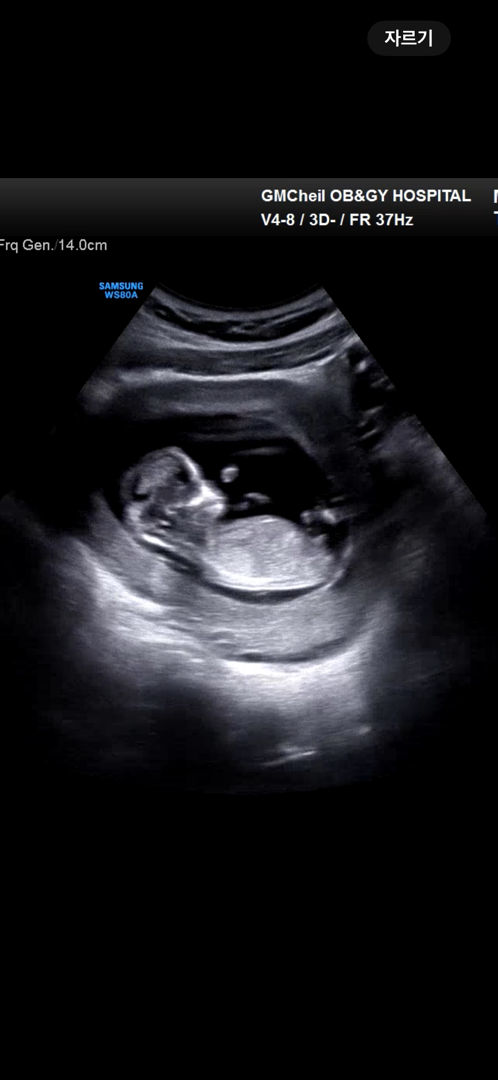

12주 각도법 봐주세용🙏🏻

아들인 것 같은데... 어떻게 보시나요~

아들!

저도 아들로 보여용!

빼박 아들이네용ㅎㅎ귀여워용